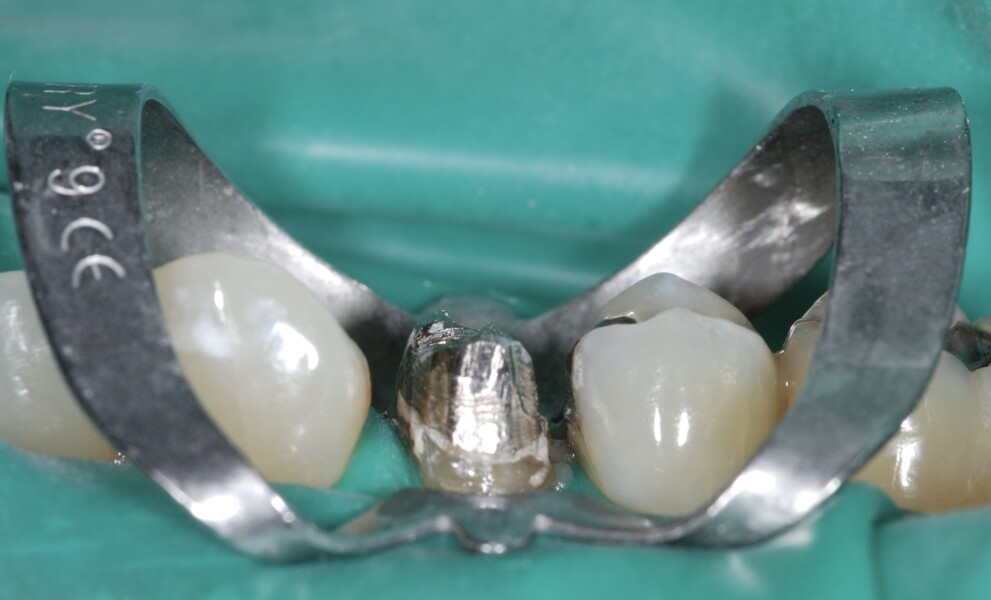

D’un point de vue pratique, la première étape consiste à réduire les dimensions du tenon s’il occupe une grande partie de la structure coronaire, de préférence en lui donnant une forme cylindrique similaire à celle d’un tenon préfabriqué. De même, une reconstitution corono-radiculaire coulée ancrée dans plusieurs canaux doit d’abord être sectionnée jusqu’au niveau du plancher de la cavité pulpaire, afin de la traiter comme un ensemble de tenons unitaires, ce qui diminue le degré de rétention global du système. La réduction du tenon doit être effectuée avec des fraises en carbure spécialement conçues pour découper le métal, sous une irrigation abondante. Les évaluations cliniques et radiographies préliminaires sont essentielles pour planifier l’angle de coupe. La procédure doit être fréquemment vérifiée et, si nécessaire, il convient d’effectuer des contrôles radiographiques avant qu’une quantité excessive de dentine ne soit sacrifiée (Figs. 1–3).

Fig. 1 : Radiographie préopératoire montrant la présence d’une reconstitution corono-radiculaire coulée, ancrée dans les trois canaux.